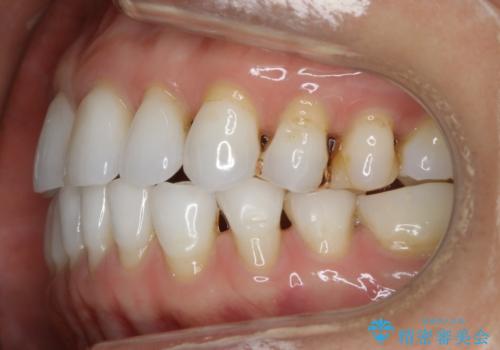

- 歯ぎしりや食いしばり、噛み合わせの治療とガタつきを治したいとのことでご来院されました。

検査の結果、前歯と臼歯の高さに差があり、前歯が全く当たらない状態になっているため歯ぎしりによって奥歯が削れてしまっているという状態でした。

マウスピースの矯正装置を用い、ガタつきを治しつつ奥歯を沈めていくことで噛み合わせ全体の改善を図りました。